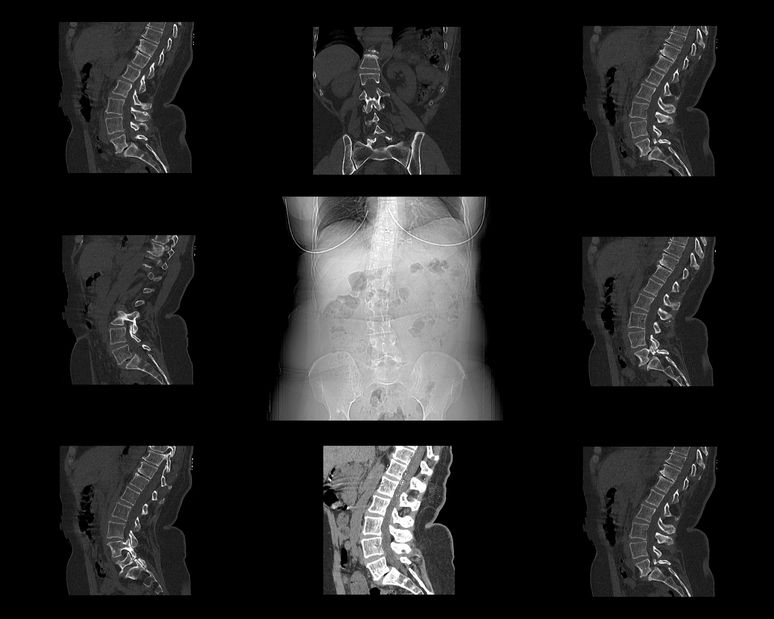

Leczenie zespołów bólowych kręgosłupa w przebiegu dyskopatii

W chorobach kręgosłupa i związanych z nimi zespołach bólowych przez bardzo długi okres możliwe jest uzyskanie poprawy przez samo tylko wyeliminowanie przyczyn, które prowadzą do powstawania bólów. Częstymi przyczynami powstawania zmian w kręgosłupie lub czynnikami nasilającymi istniejące zmiany są przeciążenia statyczne i dynamiczne.